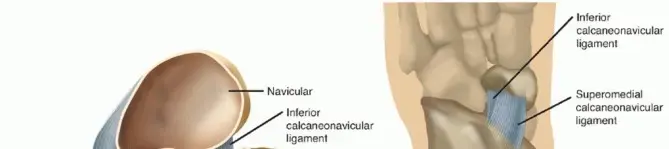

لفهم طبيعة ائتلاف عظام الرسغ وآثاره، من الضروري أولاً التعرف على التشريح الأساسي لعظام الكاحل والقدم، خاصة المفصل تحت الكاحل.

تتكون القدم من 26 عظمة معقدة تتفاعل مع بعضها البعض لتوفير الدعم والثبات والمرونة اللازمة للحركة. تنقسم هذه العظام إلى ثلاث مجموعات رئيسية:

عظام الرسغ (Tarsals):

وهي سبع عظام كبيرة في الجزء الخلفي والأوسط من القدم، وتشمل عظم الكاحل (Talus)، وعظم العقب (Calcaneus)، والعظم الزورقي (Navicular)، والعظم المكعبي (Cuboid)، وثلاثة عظام إسفينية (Cuneiforms).

المفصل تحت الكاحل ودوره

يُعد المفصل تحت الكاحل (Subtalar Joint) واحدًا من أهم المفاصل في القدم، ويتكون من التقاء عظم الكاحل (Talus) مع عظم العقب (Calcaneus). يسمح هذا المفصل بحركات الانقلاب (Inversion) والانقلاب للخارج (Eversion) للقدم، وهي حركات ضرورية للتكيف مع الأسطح غير المستوية والحفاظ على التوازن أثناء المشي والجري. عندما يكون هناك ائتلاف في هذا المفصل أو في المفاصل المجاورة، فإن هذه الحركات تصبح محدودة أو معدومة، مما يؤدي إلى الألم والخلل الوظيفي.